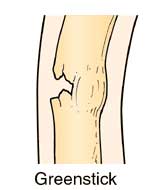

Greenstick Fracture:

The bone cracks one side only, not all the way through (like when trying to bend a living stick

on a tree), usually only seen in children due to the softness of their bones